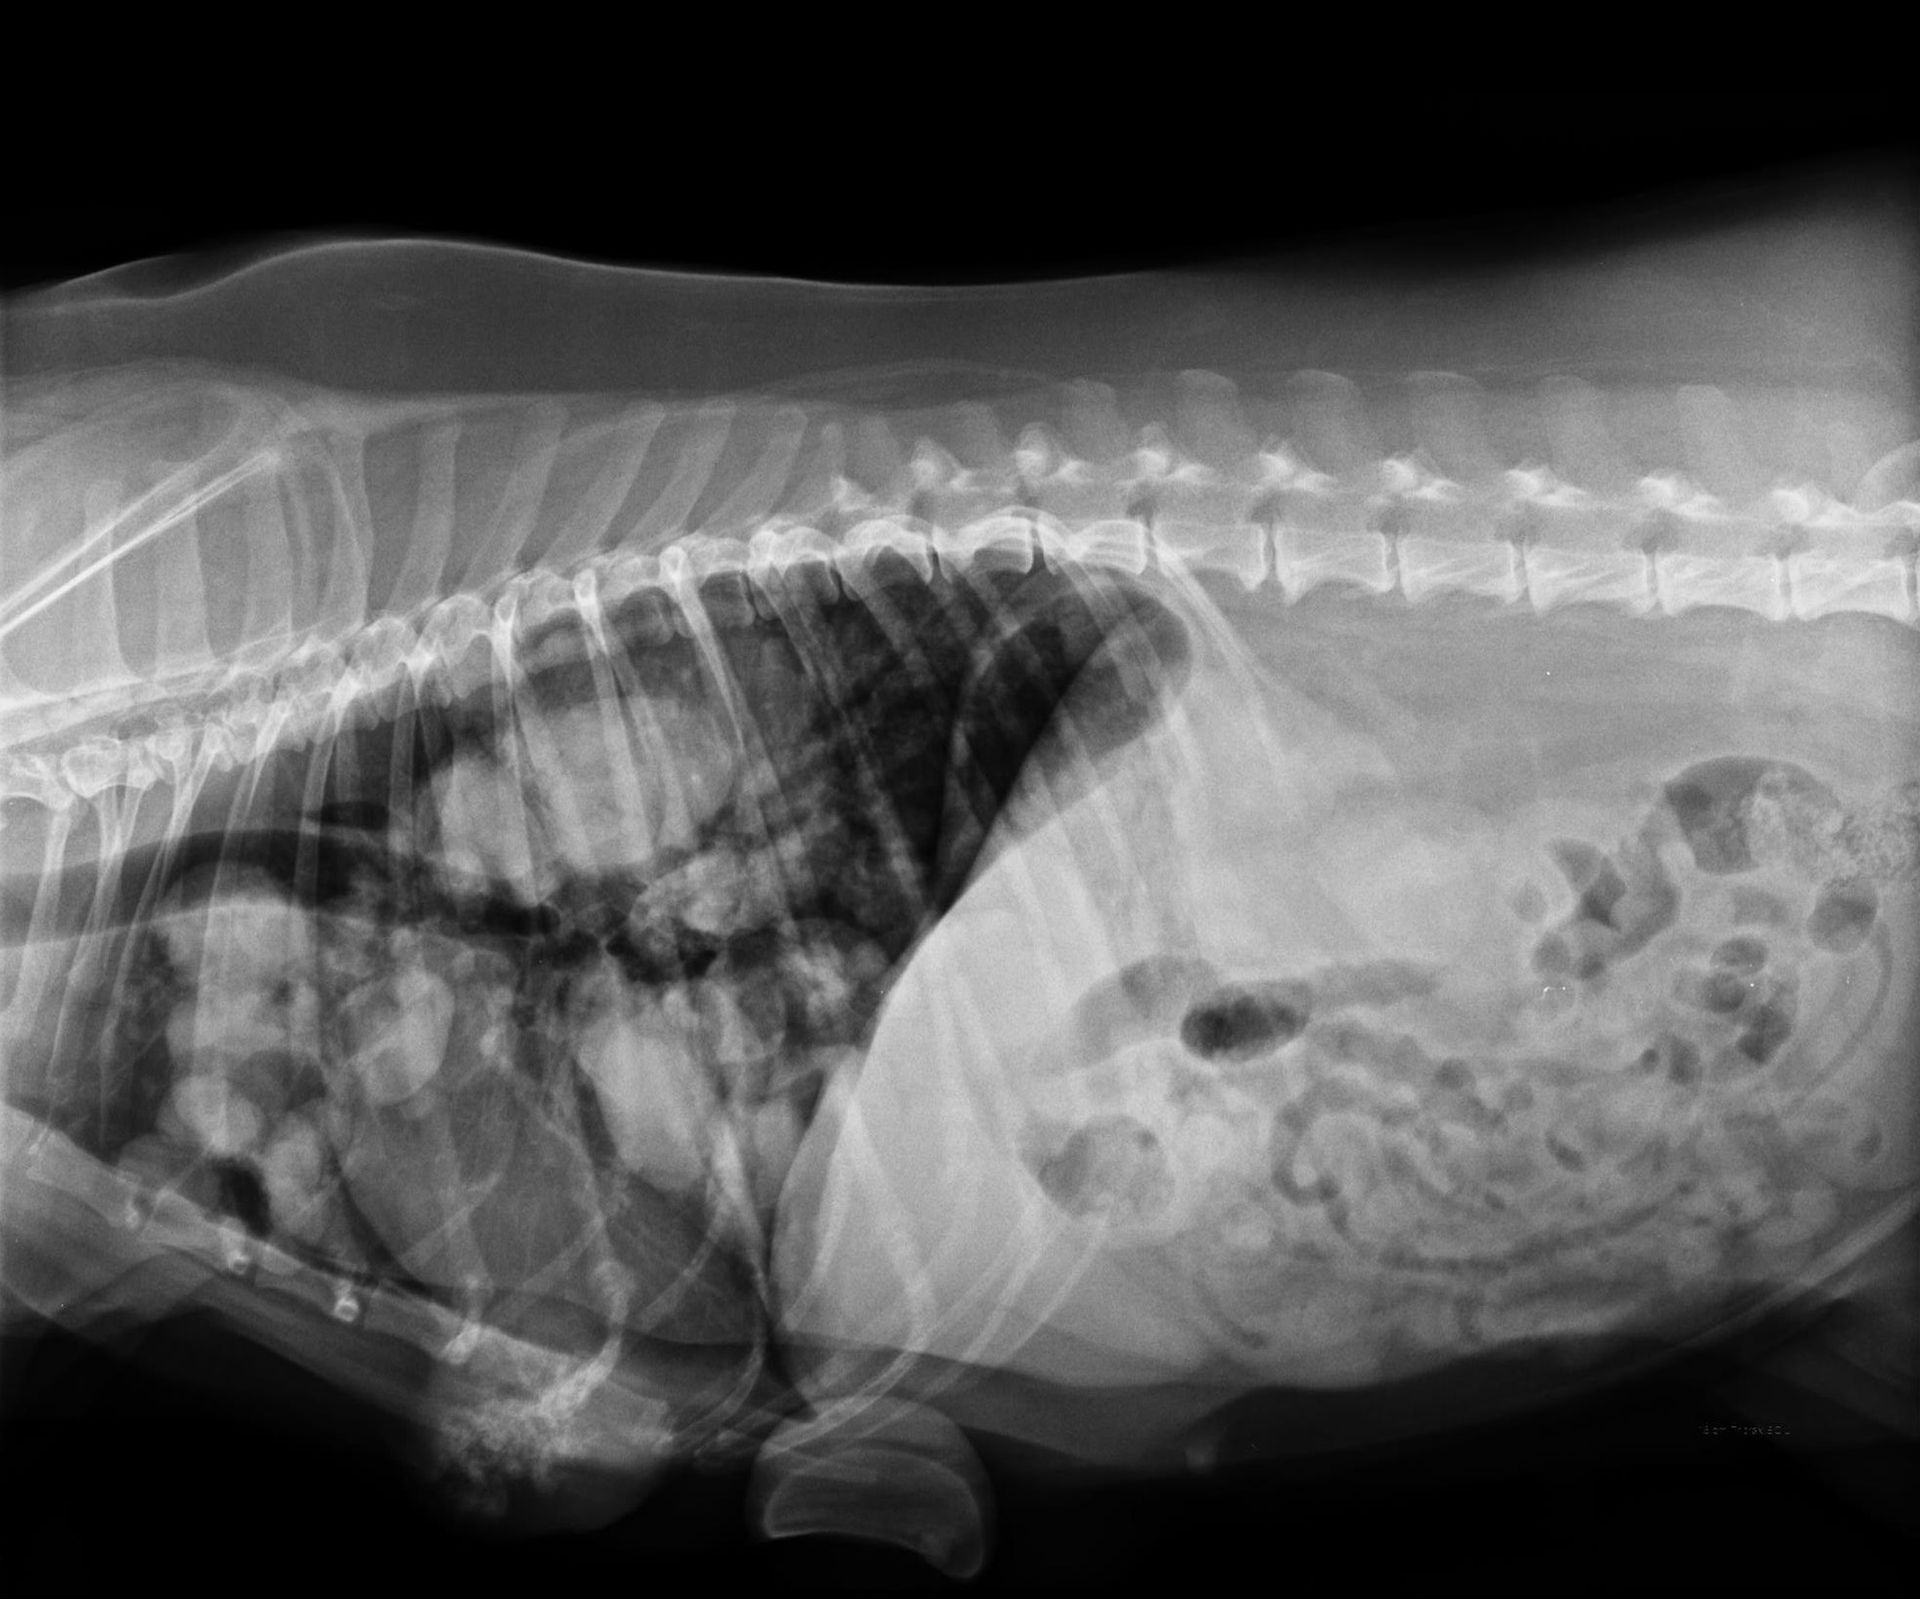

L'imagerie reste un examen complémentaire de choix en médecine vétérinaire. De nouvelles techniques se sont développées comme le Scanner ou l'IRM que l'on peut dorénavant retrouver dans des Centres Hospitaliers Vétérinaires. Cependant, la radiologie ainsi que l'échographie demeurent des examens de première intention qui permettent de diagnostiquer un certain nombre de pathologies le jour de la consultation si nécessaire.

La clinique est équipée d'un générateur radio ainsi que d'un développement numérique. Ce type de développement est rapide, sans utilisation de produits chimiques et permet d'obtenir les images sur un écran d'ordinateur. La définition des radios est ainsi meilleure. Nous pouvons aussi facilement vous faire parvenir les radios de votre animal ou les transférer à un confrère le cas échéant par mail.

- Radios classiques